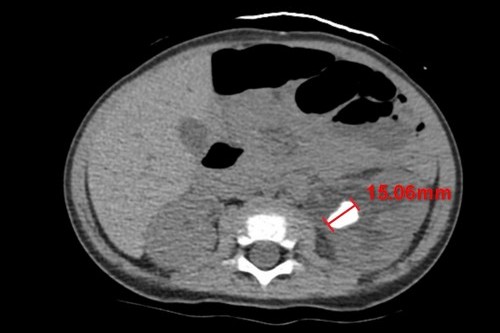

圖說:電腦斷層不同切面顯示,余小弟體內有兩顆約1.5公分大的結石。

二零二二年七月二十五日,花蓮慈濟醫院完成院史上個案年紀最小的腎結石取出手術!年僅十一個月大的男嬰體內長出兩顆約1.5公分的腎結石並造成急性腎臟發炎,小兒腎臟科主任陳明群醫師指出,查找文獻資料也極少在年紀這麼小的孩子身上發現長有這麼大顆的腎結石的紀錄,這種情況相當罕見,因而如何將石頭順利拿出並取乾淨,對醫療團隊也是個挑戰。

今年七月初,出生僅十一個月的余小弟因發燒就醫,原先以為只是單純的泌尿道感染,沒想到照了腎臟超音波,發現腎臟裡有兩顆超過一公分的結石,其中一顆堵在輸尿管與腎臟的銜接處,造成堵塞與腎水腫。余小弟的媽媽表示,早在今年三、四月的時候孩子就曾因泌尿道感染而發燒,到其他醫院治療,當時透過藥物控制下來,燒退後就回家了,沒想到這次又再發生。